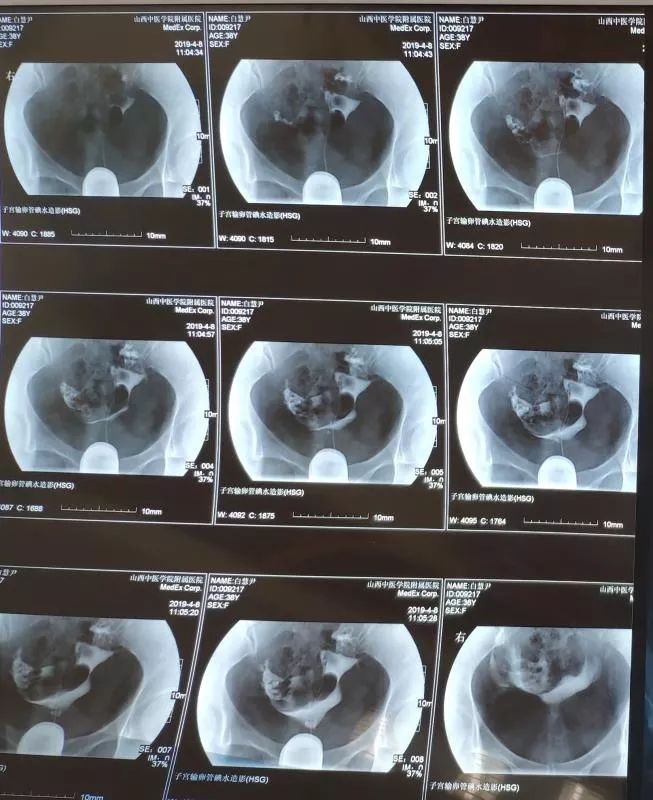

在不孕不育科中药内服+外治(中药保留灌肠+热敷)治疗三个月后,复查子宫输卵管造影:双侧输卵管通而不畅,造影剂弥散均匀,该患者经治疗后输卵管由不通转为通畅。